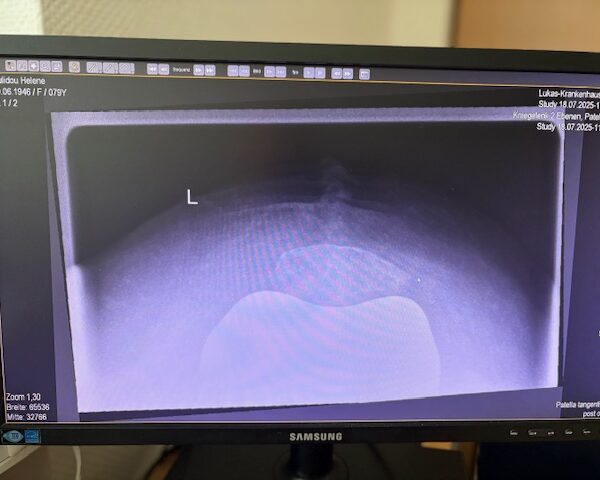

Η 80χρονη ασθενής παρουσίαζε έντονο πόνο και δυσκαμψία στο αριστερό γόνατο τα τελευταία χρόνια. Ο πόνος είχε επιδεινωθεί, επηρεάζοντας τη βάδιση και τη συνολική κινητικότητα, ενώ δυσκολευόταν ακόμα και σε απλές δραστηριότητες όπως το ανέβασμα σκαλοπατιών ή το περπάτημα σε μικρές αποστάσεις. Με την υπάρχουσα πρόθεση ισχίου στην αριστερή πλευρά η ασθενής ήταν αρκετά ευχαριστημένη. Ο ακτινολογικός και κλινικός έλεγχος ανέδειξε προχωρημένη οστεοαρθρίτιδα του αριστερού γόνατος, με πλήρη απώλεια του αρθρικού χόνδρου και παραμόρφωση του μηροκνημιαίου άξονα. Μετά από ανάλυση όλων των επιλογών, αποφασίστηκε η Ολική Αρθροπλαστική Γόνατος με Ρομποτική Υποβοήθηση, με στόχο την απόλυτη ακρίβεια στην τοποθέτηση των εμφυτευμάτων και την αποκατάσταση της φυσιολογικής μηχανικής του γόνατος.

Ο προεγχειρητικός ψηφιακός σχεδιασμός

Πραγματοποιήθηκε σε ειδική ακτινογραφία ολόκληρων των δύο κάτω άκρων. Σε αυτό το ψηφιακό μοντέλο σχεδιάστηκε με ακρίβεια το είδος, το μέγεθος και η ακριβής θέση των προθέσεων, με βάση τα ανατομικά χαρακτηριστικά της ασθενούς.